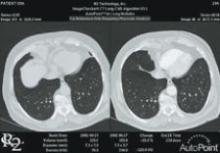

The prevalence of lung cancer in the U.S., and the world for that matter, is a major public health and economic concern. Attributed primarily to cigarette smoking, lung cancer is usually diagnosed well into the latter stages of metastasis, meaning the deadly cancerous part of the tumor has already differentiated and separated from its origin and into the bloodstream. For decades, one of the primary diagnostic imaging tools to uncover lung tumors has been a chest X-ray.